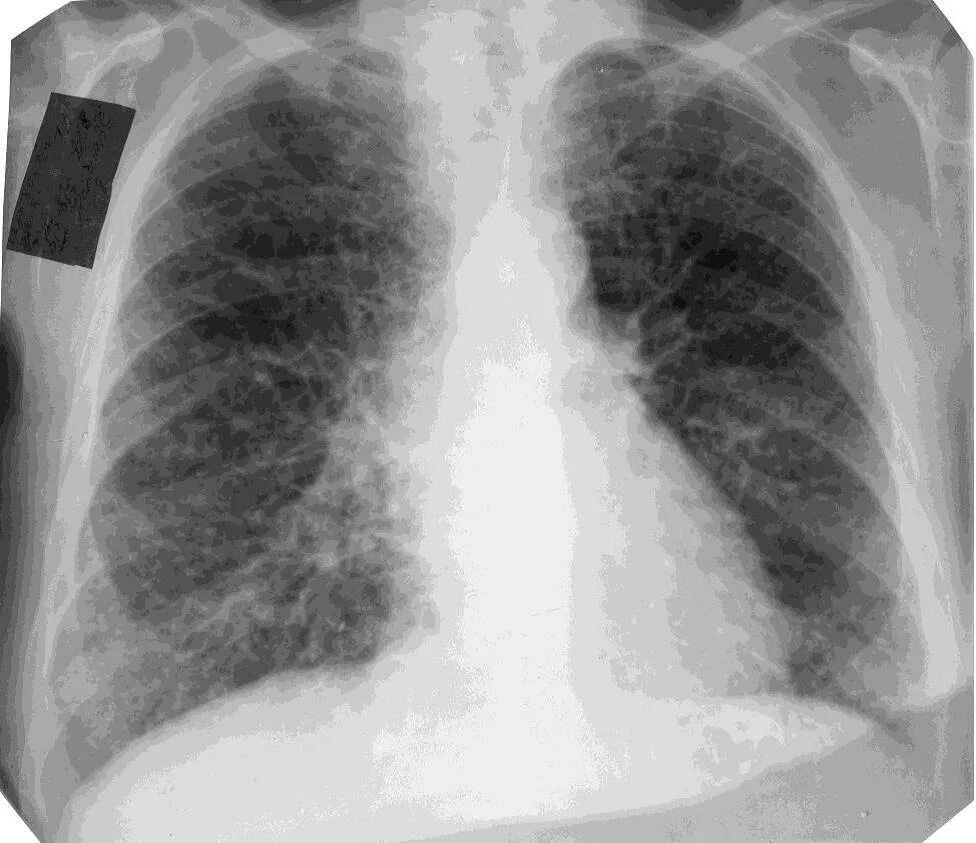

Пневмосклероз рентгенограмма